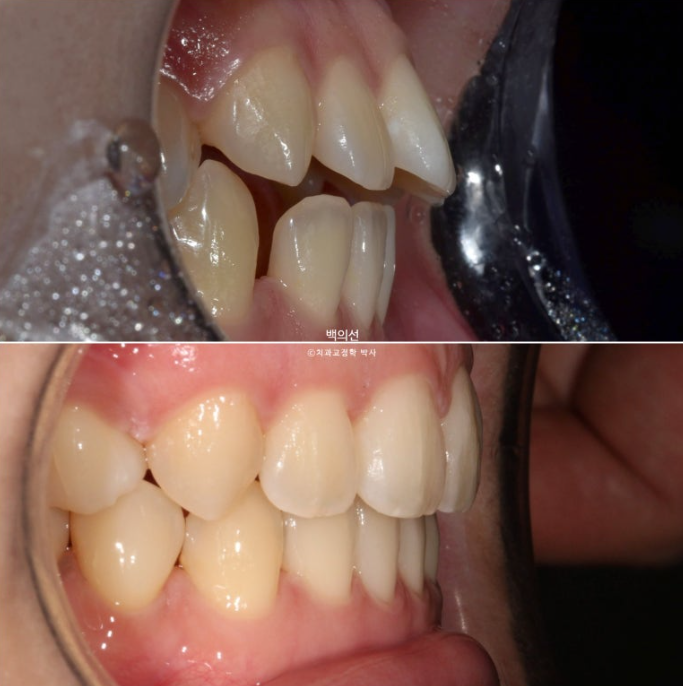

23.01~25.07

어금니 교합이 기존 3급에서 정1급 교합관계로 바뀌었습니다.

뻗쳐있던 위 앞니가 해소가 되면서 돌출이 해소되었습니다.